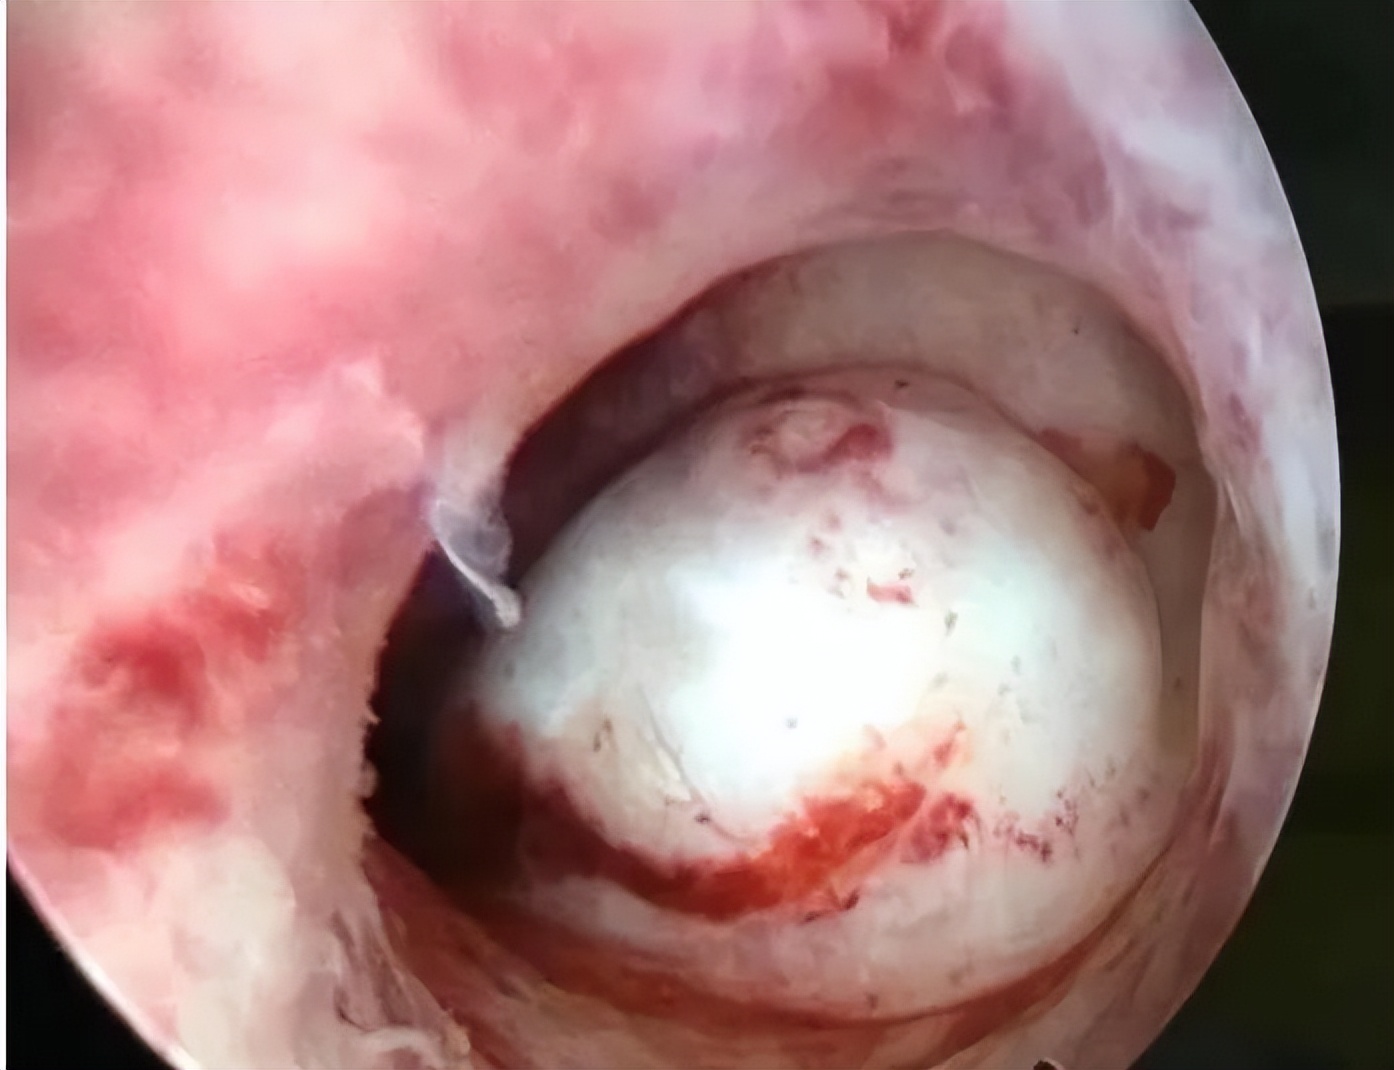

2)宫腔粘连、子宫畸形;

子宫黏膜下肌瘤

7)宫腔镜术后相关评估,如子宫内膜粘连分解术后、子宫纵隔切除术后。